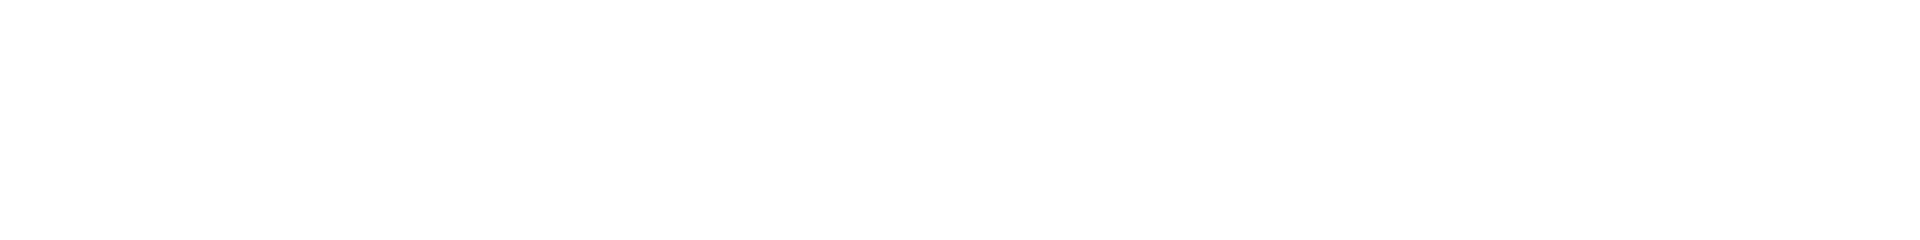

OSTEOSARKOM

Osteosarkom Nedir?

Osteosarkom, mikroskop altında incelendiğinde immatür (olgunlaşmamış) kemik üretimi ile karakter...